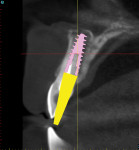

When a tooth is fractured or requires extraction, a dental implant is the only treatment option that will restore the root of the tooth, which can provide support for a new clinical crown. A CBCT scan can provide an accurate 3D-reconstructed volume as an aid in planning for an implant-supported restoration (Figure 1). The cross-sectional image reveals the precise location of the root within the alveolus, provides information on bone density, and shows that the tooth had previous root canal therapy (Figure 2). The axial image is important to help determine the morphology of the tooth root based upon the inferior-superior location of the slice (Figure 3). Depending on the interactive treatment planning software, the use of realistic manufacturer-specific virtual implants of known length and diameter can be simulated within the receptor site (Figure 4). The yellow projection is a helpful tool to aid the clinician in establishing the proper trajectory of the implant within the cross-sectional image and in relation to the desired restorative option (ie, screw- or cement-retained). It should be noted that this is only one slice, and that the final positioning of the implant should be determined only after all views have been considered.